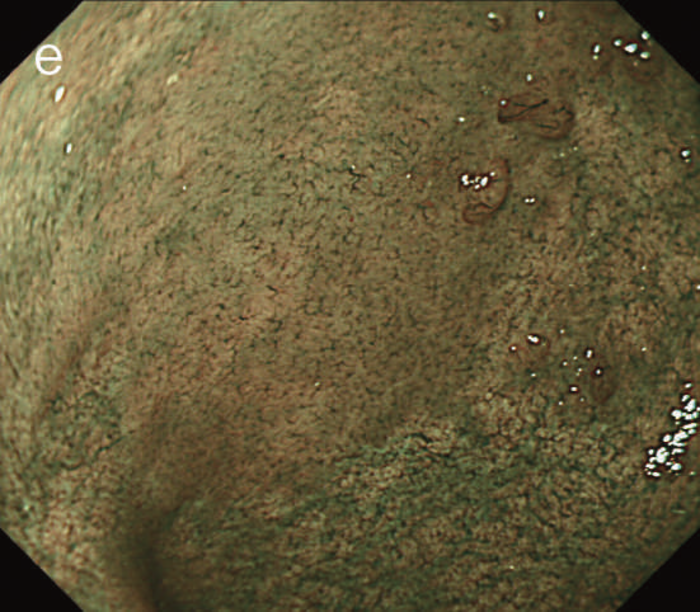

図6 UC関連LGDの内視鏡所見

- 白色光像:直腸(下部直腸)に色調変化は乏しく,微小な隆起を複数認めた。背景粘膜は寛解期にあった。

- NBI非拡大像:Brownishな領域が明らかとなった。

- 色素内視鏡像:病変辺縁が明瞭な微小な隆起を複数伴う表面平坦型病変。

- NBI拡大像:口径整でらせん状の微小血管と絨毛状の表面構造を認めた。

- pit pattern像:小型の類円形,管状pitを認めた。